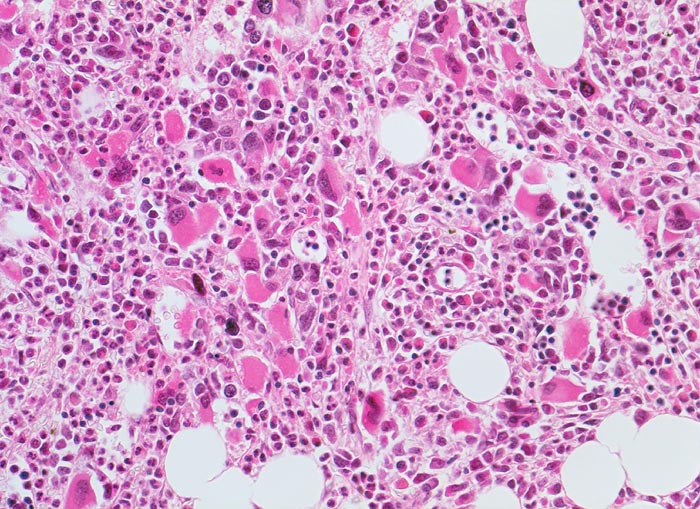

- Vermehrung von atypischen, in Gruppen liegenden Megakaryozyten mit abnorm lobulierten Kernen.

- Nacktkernige (zytoplasmaarme) und vergrösserte Megakaryozyten.

- Hyperplastische ausreifende Myelopoese.

- Hypoplastische Erythropoese.

Die Erkrankung ist charakterisiert durch Knochenmarkfibrose, Hepato-Splenomegalie und extramedulläre Blutbildung. Diese findet sich am häufigsten in Leber und Milz, seltener in Lymphknoten, Nieren, Nebennieren, Dura mater, Gastrointestinaltrakt, Lunge, Mamma oder Haut. Blut und Knochenmark sind immer involviert. Die Krankheit entwickelt sich über ein initiales präfibrotisches Stadium mit hyperzellulärem Knochenmark zum fibrotischem Stadium (vorliegendes Präparat). Das fibrotische Stadium ist gekennzeichnet durch eine Vermehrung von Reticulin- und/oder Kollagenfasern und oft einer Knochenneubildung (=Osteomyelosklerose). Die Zellularität des Knochenmarks ist dann vermindert und dilatierte Marksinus enthalten intraluminale Blutbildungsherde. Es besteht eine auffallende Proliferation von Gruppen bildenden atypischen Megakaryozyten.